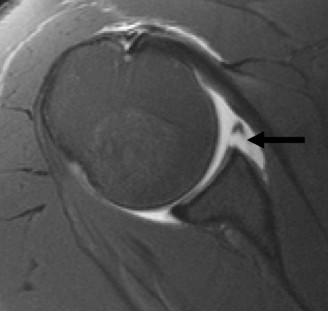

Identify the muscles that compose the force couples in the transverse and coronal planes? CASE 3 A 35-year-old male has had left shoulder pain for 4 months, ever since a low-speed motor vehicle accident (MVA). Physical examination demonstrates preserved range of motion but pain and some weakness with Jobe’s testing. His imaging is shown in Figure 2–8.

Figure 2–8_Reproduced with permission from Stadnick ME. _Partial Rotator Cuff Tears. MRI Web Clinic. 2007 (Apr).

What is the most likely diagnosis?

The correct answer is (A). These are best diagnosed on an MRI as seen in the imaging provided; addition of intra-articular contrast can further improve this study. Answer B, full-thickness rotator cuff tear, is incorrect as the bursal side of the tendon can be seen to be in continuity. Answer C, a SLAP lesion, will be visualized as a labral tear on a coronal MRI and will be found at the biceps root. Answer D, an ALPSA lesion, will be most clearly seen on an axial MRI. It is a variant of a Bankart lesion where the labrum is displaced medially and inferiorly rolling down the glenoid neck underneath the periosteum.

MRI remains the most popular imaging modality for diagnosing rotator cuff tears. Normal rotator cuff tendon appears dark on both T1 and T2 sequences. Tears may be noted as being full-thickness, articular-sided, bursal-sided, or intrasubstance. They are visualized as a disruption in the regular contour of the tendon and increased signal intensity on T2 sequences. Occasionally, an MR arthrogram may provide additional information regarding a cuff tear, although this is not routinely ordered.

What MRI sequence and plane is best for viewing supraspinatus rotator cuff tears?

The correct answer is (D). T2 sequence causes most soft tissues, including muscle and tendon, to appear dark and inflammation, such as at the site of a tear, to appear bright. This means that if there is a rotator cuff tear, there will be a bright spot along the course of the dark rotator cuff tendon. This is easiest to pick out in the coronal plane because the tendon runs in this plane, allowing one to view the entire supraspinatus tendon and tear in one cut.